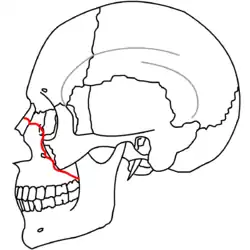

A principios del siglo XX, René Le Fort trazó ubicaciones típicas para las fracturas faciales, éstas ahora son conocidas como I, II y III fracturas de Le Fort (derecha).[5][2][6]

La fractura de Le Fort tipo II, también llamada fractura piramidal del maxilar,[7][10] cruza los huesos nasales y el reborde orbitario.[9]